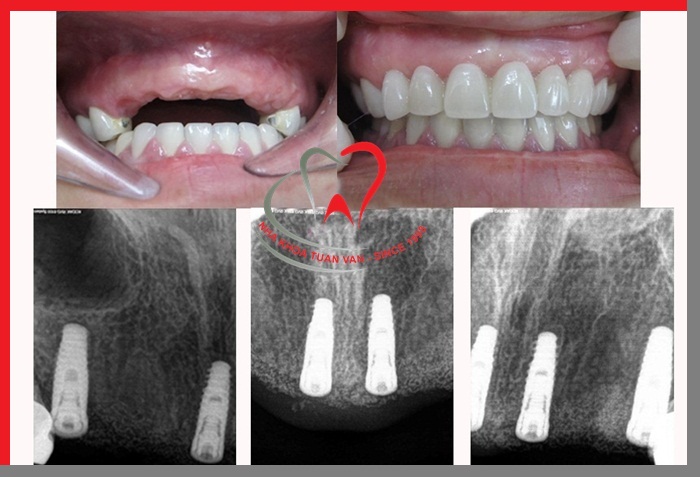

Trước và sau khi cấy ghép Implant